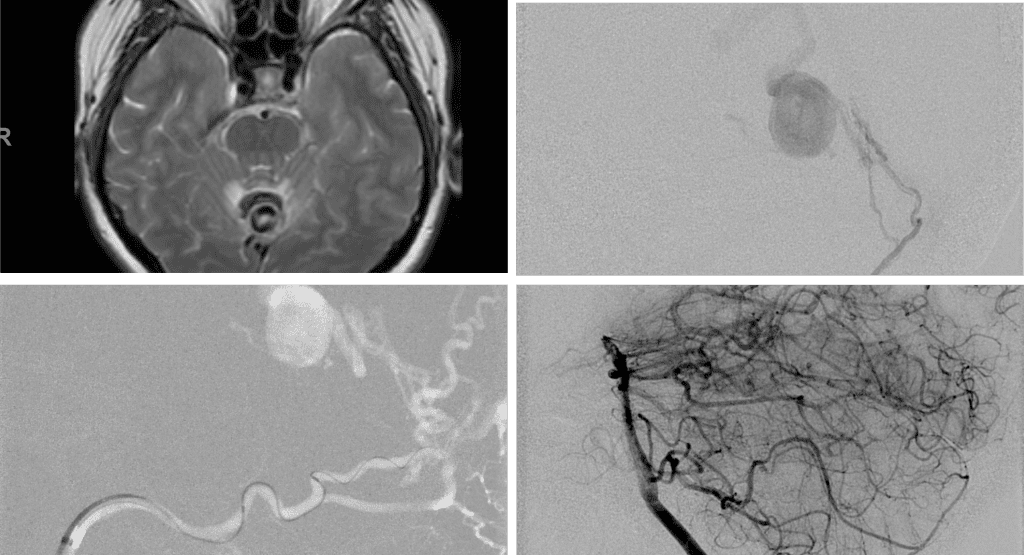

No severe neurologic deficits were observed initially. Her cerebral angiogram revealed a high flow Dural arterial venous fistulous malformation of the tentorium supplied by the bilateral external carotid and left vertebral arteries into a large venous varix within the fourth ventricle at the site of the hemorrhage. Deep venous drainage is observed into the Galenic and Straight Sinus of the posterior fossa (Figure 2).

Figure 2. [A] Ruptured Varix/Aneurysm of the Deep Venous Posterior Fossa drainage and AV shunting (arrows) [B] Posterior Meningeal Artery Fistula [C] Right Middle Meningeal Artery Fistula [D] Post embolization Left Vertebral Angiogram demonstrates resolution of the high flow and pressure A-V Shunting following successful embolization with liquid embolic (NBCA).

Embolization was successful at immediately reducing the pressure into the Aneurysmal Varix with greater than 90% reduction in A-V shunts. After an intensive period of critical care monitoring and care for her initial brain hemorrhage, she made a near complete recovery with mild intermittent left sided paresthesias and generalized deconditioning. After receiving inpatient and outpatient Acute Rehabilitation, Physical, and Occupational therapy, she completely recovered all of her Activities of Daily Living (ADLs) at 3 months and achieved an modified Rankin Scale (mRS) of 0. On follow-up angiography, small residual low flow A-V shunts were identified and targeted for Gamma Knife Radiosurgery (Figure 5 and 6).